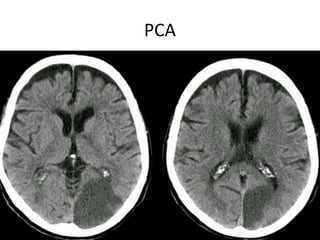

PCA